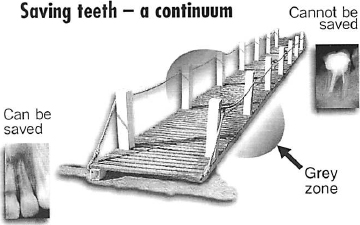

SAVING TEETH – A CONTINUUM

I would like to put to you the concept that ‘What can and what can’t be saved’ is actually a continuum (Fig. 2). You might imagine the problem as a walkway with one end on safe, firm ground and the other end precariously balanced and unsupported. At one end of the walkway, represented by that on secure ground, certain teeth can be saved with a very high probability of success. At the other end, represented by the precariously balanced part of the walkway, there are some teeth that definitely cannot be saved.

The area of most interest and challenge is a grey zone, roughly in the middle. That is where difficult decisions must be made about whether or not the tooth can be saved. In a paradoxical way, the more you approach the centre and try to define where the tooth is in this grey zone, the harder it is to determine or predict the outcome of treatment.

It seems reasonable to assume that the vast majority of teeth fall into the category represented by the walkway on secure ground, that is teeth that can be saved. What I shall address as we transverse the walkway are two main areas. Firstly, what are the limitations of our success rate from a biological point of view? Secondly, what clinical factors help you to determine whether you might treat, refer, or extract the tooth?

Fig. 2.–The problem of saving teeth can be regarded as a continuum, represented as a path or walkway. At one end, bottom left, teeth can be saved with a high change of success and at the other end, top right, some teeth cannot be saved. The most challenging clinical decisions are in a middle, grey zone where the outcome of treatment is uncertain.